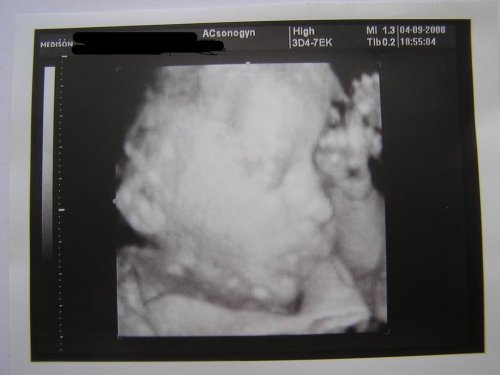

nasa Veronika, 27 0 tt, 1030 gramov